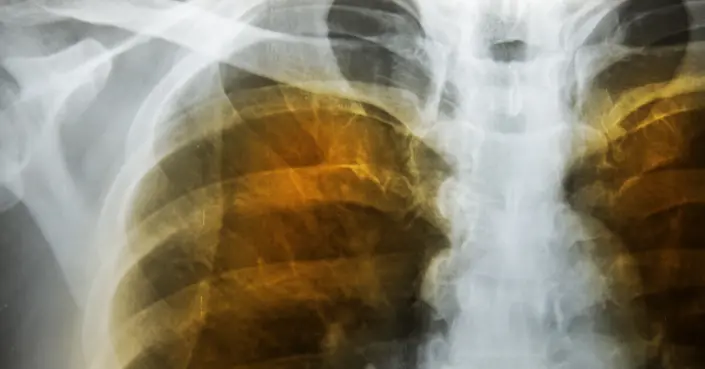

- التصوير بالأشعة السينية (X-ray) والتصوير المقطعي المحوسب (CT scan): هذه الفحوصات التصويرية توفر صوراً مفصلة لرئتيك، مما يساعد الأطباء على رؤية التلف الحاصل في الحويصلات الهوائية واستبعاد حالات أخرى.